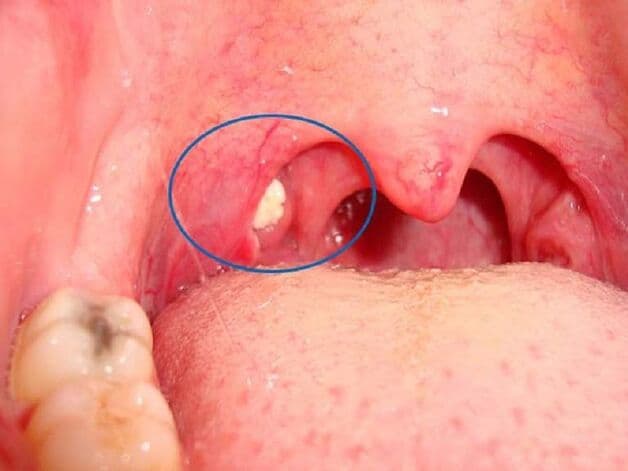

Sỏi amidan là những khối màu trắng hoặc vàng xuất hiện trên bề mặt amidan. Được đánh giá là không gây nguy hiểm cho cơ thể nhưng sẽ tạo cảm giác khó chịu trong quá trình ăn uống, nói chuyện. Và các sỏi amidan này thường dễ quan sát bằng mắt thường qua gương nhỏ.

– Nhìn thấy các chấm trắng nhỏ ở amidan khi quan sát qua gương

Sỏi amidan là những đốm trắng, vàng và dễ nhìn thấy khi quan sát qua gương